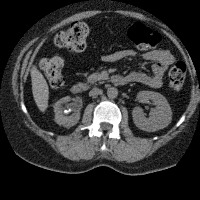

Regiao Renal

RegiaoRenal

regiao_renal